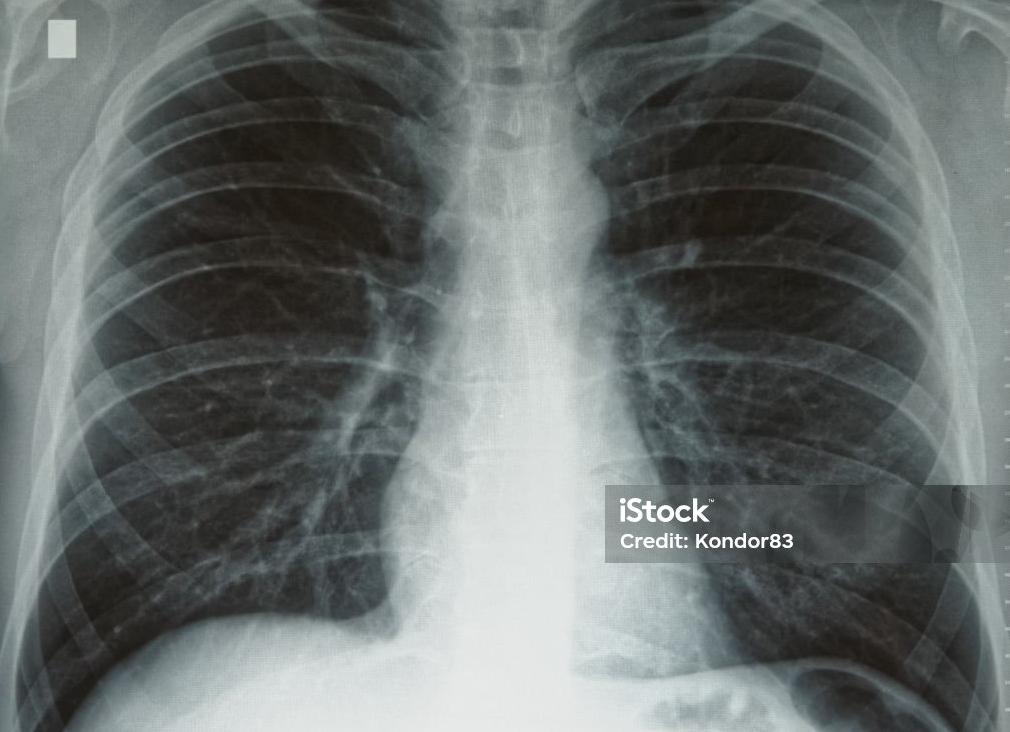

Снимки легких у здоровых и больных пациентов отображают одни и те же структуры: легочные поля с обеих сторон от позвоночного столба, в центре – тень от сердца, в верхней части снимка видны ключицы, а в нижней части – купол диафрагмы. На легочные поля проецируются тени ребер.

При рассмотрении рентгена легких здорового человека врачи оценивают состояние мягких и костных тканей, диафрагмы и реберно-диафрагмальных синусов, средостения.

Рентген легких здорового человека описывают по классическому стандарту. В первую очередь вносят данные о состоянии легочных полей, затем описывают корни легких, диафрагмальные купола и реберно-диафрагмальные синусы, потом оценивают состояние сердечной тени и мягких тканей.

Пример описания нормальной рентгенограммы легких:

• В легочных полях отсутствуют видимые очаговые и инфильтративные тени.

• Корни нормальных размеров, структурны, не расширены.

• Контуры диафрагмально-реберных синусов и диафрагмы без патологий.

• Тень сердца обычной формы.

• Мягкие ткани без особенностей.

В норме на снимках купола диафрагмы расположены на уровне шестых ребер, при этом правый купол немного выше. В центре снимка нередко можно увидеть два или три грудных позвонка, остистые отростки которых в норме лежат между ключицами на равном расстоянии от них. Также в центре должна проецироваться тень трахеи, тень сердца в норме должна выступать справа не более чем на 1 см, а с левой стороны она не должна заходить дальше среднеключичной линии.

Корнями легких условно называют бронхиальные разветвления в легочной ткани, в норме они имеют четкую структуру. В них могут быть обнаружены увеличенные лимфатические узлы. Сосудистый рисунок не прослеживается в периферических отделах легких. Реберно-диафрагмальные синусы должны быть свободные.